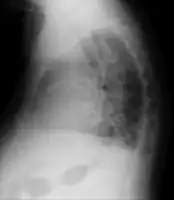

Acute pulmonary edema

Acute pulmonary edema lateral

Low oxygen saturation and disturbed arterial blood gas readings support the proposed diagnosis by suggesting a pulmonary shunt. A chest X-ray will show fluid in the alveolar walls, Kerley B lines, increased vascular shadowing in a classical batwing peri-hilum pattern, upper lobe diversion (increased blood flow to the superior parts of the lung), and possibly pleural effusions. In contrast, patchy alveolar infiltrates are more typically associated with noncardiogenic edema[8]